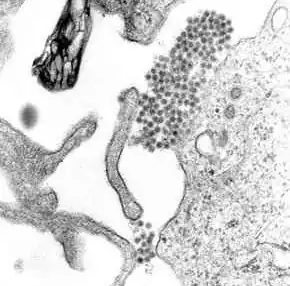

Dengue virus (DENV) is an RNA virus of the family Flaviviridae; genus Flavivirus. Other members of the same genus include yellow fever virus, West Nile virus, and Zika virus. Dengue virus genome (genetic material) contains about 11,000 nucleotide bases, which code for the three structural protein molecules (C, prM and E) that form the virus particle and seven other protein molecules that are required for replication of the virus.[30][31] There are four confirmed strains of the virus, called serotypes, referred to as DENV-1, DENV-2, DENV-3 and DENV-4. The distinctions between the serotypes are based on their antigenicity.[32]

For 2 to 10 days after becoming newly infected, a person's bloodstream will contain a high level of virus particles (the viremic period). A female mosquito that takes a blood meal from the infected host then propagates the virus in the cells lining its gut.[40] Over the next few days, the virus spreads to other tissues including the mosquito's salivary glands and is released into its saliva. Next time the mosquito feeds, the infectious saliva will be injected into the bloodstream of its victim, thus spreading the disease.[41] The virus seems to have no detrimental effect on the mosquito, which remains infected for life.[21]